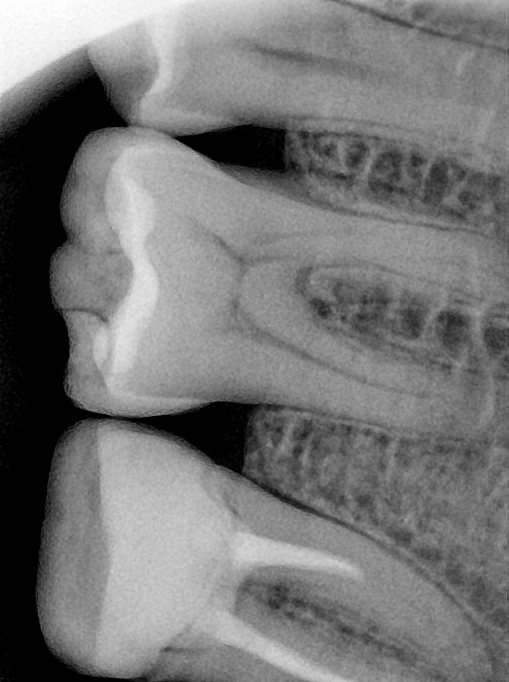

CR/DR 牙齿分割阶段记录

当前进展

- 完成了 CR/DR 牙齿相关分割训练

相关测试

遇到的问题

- 训练过程中出现过 mask 下移问题

- 部分结果会出现 box 填充异常

- mask 边缘仍然有比较明显的锯齿感

第二版算法问题测试